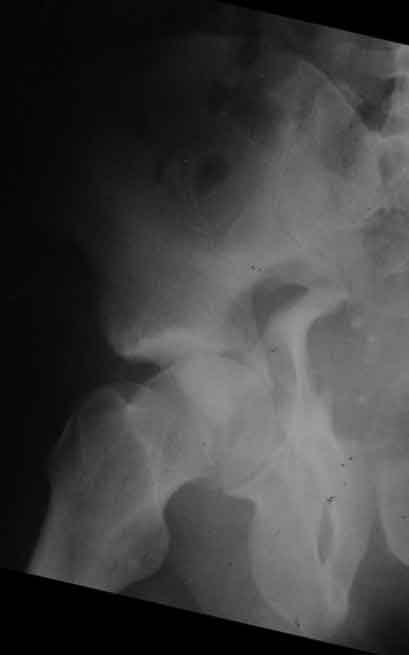

еще одно дополнение

|